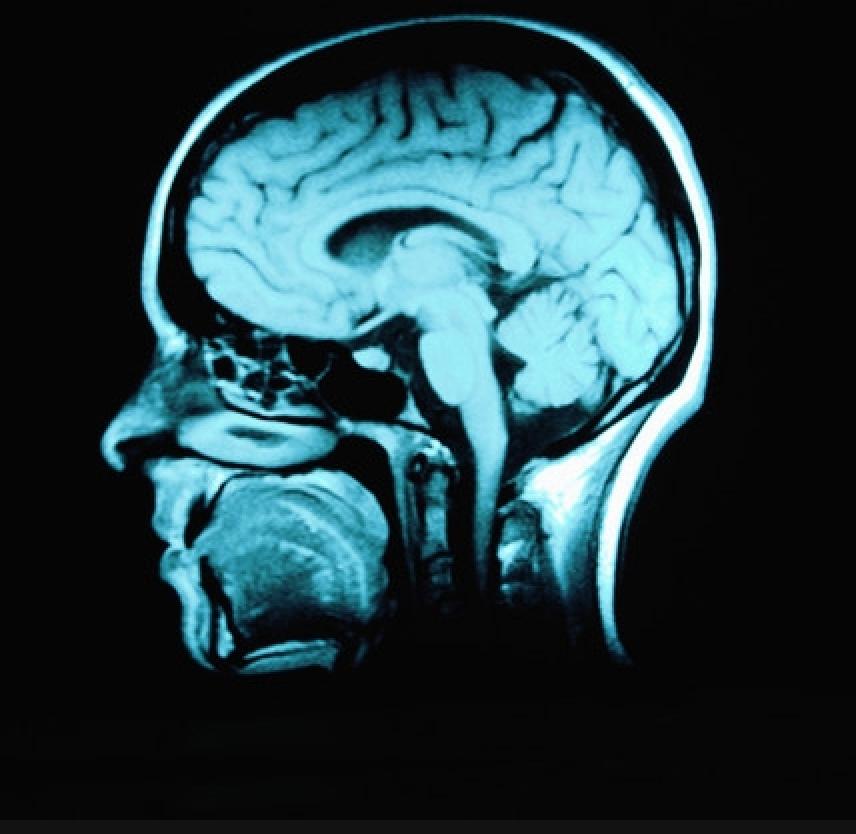

Traumatic brain injury (TBI) refers to damage or destruction of brain tissue due to a blow to the head, resulting from an assault, a car crash, a gunshot wound, a fall, or the like.

In closed head injury, damage occurs because the person receives a blow to the head that whips the head forward and back or from side to side (as in a car crash), causing the brain to collide at high velocity with the bony skull in which it is housed. This jarring bruises brain tissue and tears blood vessels, particularly where the inside surface of the skull is rough and uneven; damage occurs at (and sometimes opposite) the point of impact. Thus, specific areas of the brain - most often the frontal and temporal lobes - are damaged. This focal damage often can be detected through MRI and CAT scans.

In closed head injury, the rapid movement of the brain can also stretch and injure neuronal axons - the long threadlike arms of nerve cells in the brain that link cells to one another, that link various parts of the brain to each other and that link the brain to the rest of the body. This widespread axonal injury interrupts functional communication within and between various brain regions and sometimes between the brain and other body parts. However, this type of diffuse damage typically cannot be detected through currently available imaging technology (but with new developments, this may change). Its existence is very clear, however, in the widespread effects it has on the individual's functioning.

In sum, after a closed head injury, damage can occur both in specific brain areas (due to bruising and bleeding) and also be found throughout the brain (due to stretched or destroyed axons). The results of a closed head injury tend to affect broad areas of the individual's functioning, primarily due to the diffuse axonal injury. The extent of damage is correlated with the force of the blow to the head; for example, a head forced into a car windshield at high speed will tend to sustain more tissue damage than when the car is traveling at a slower speed.